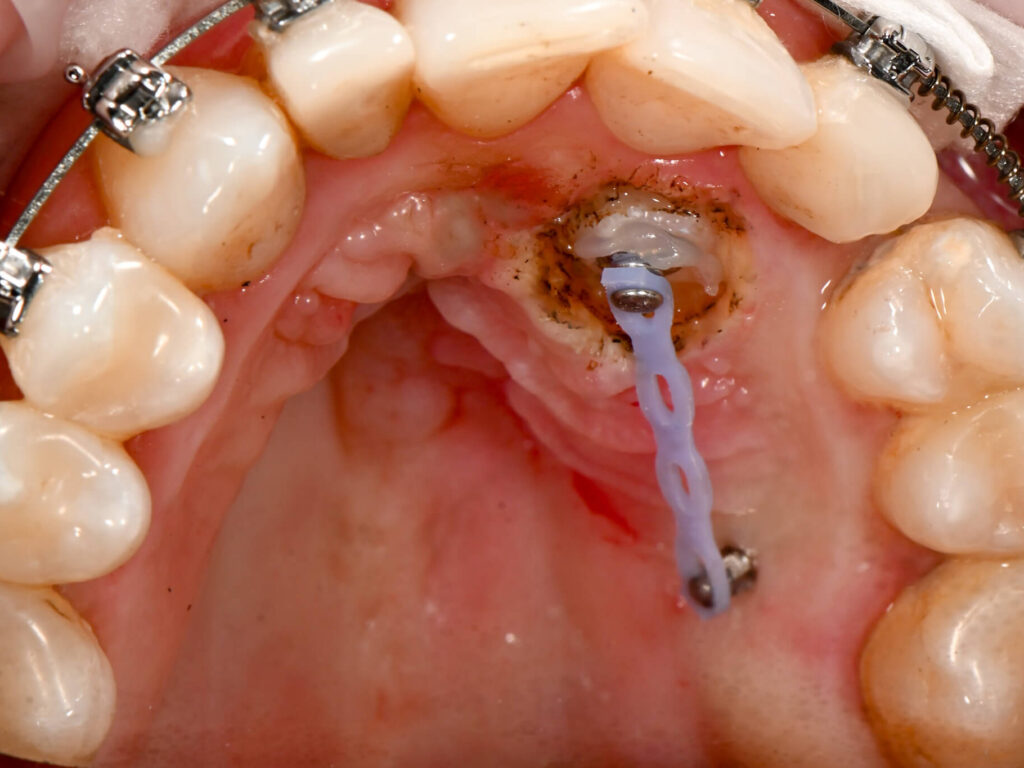

- gingiwektomia

- frenulektomia

- usuwanie przerostów tkanek miękkich

- terapia perio

- leczenie zmian naczyniowych